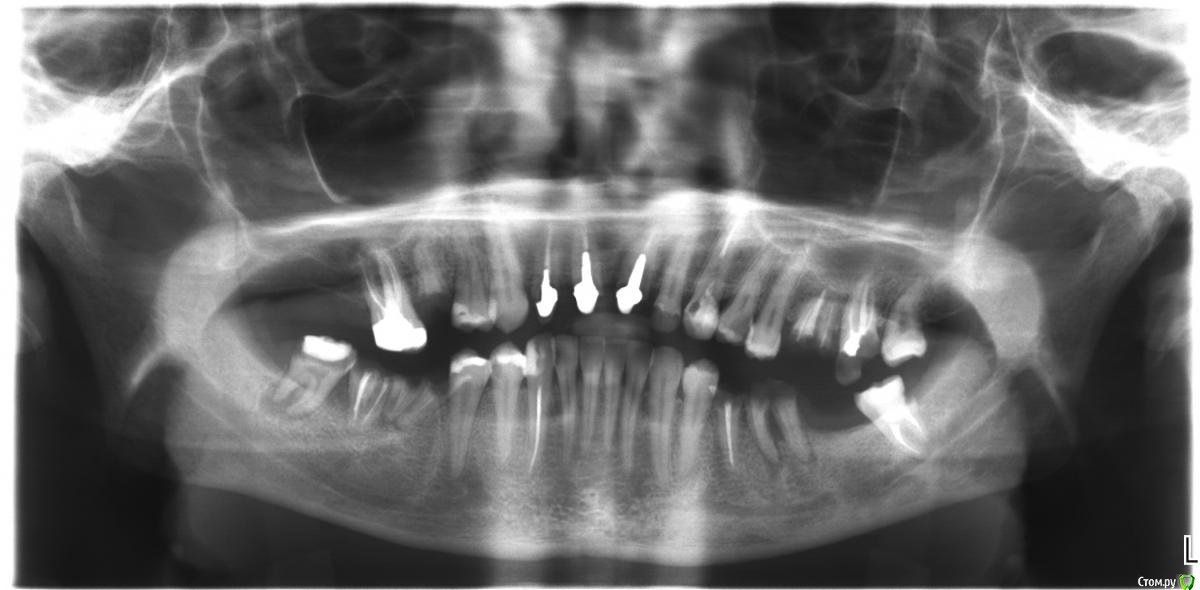

Здравствуйте, уважаемые стоматологи! Прошу оценить план лечения, предложенный протезистом. Мне 28 лет, линия улыбки высокая. Хотелось бы, чтобы протезы и коронки были незаметны для окружающих. Финансово ограничен, имплантаты потянуть не смогу.

На 11 и 21 зубах стоят спаренные пластмассовые коронки уже около 7 лет, они немного подвижны; корень 21 эти годы был чуть болезненный при нажатии на десну, и там иногда появлялась маленькая фистула. На 12 около года стояла пластмассовая коронка, она слетела и вкладка на днях вывалилась. 15, 26, 36, 43, 46, 47, 48 при жевании периодически воспаляются (или воспалялись раньше), причём 43 воспаляется редко, но когда это случается, то болит нестерпимо.

Протезист предложила: удалить 15, 12, 26, 27, 36, 46, 47, 48; на 21, 11, 12 сделать мост с нависающей частью над 12; на остальные пустые места - съёмники либо из акри-фри, либо акриловые. Уверяла, что корни 21 и 11 хорошие и выдержат консоль.

Сиреневые кружки - удалять, зелёные стрелы под вопросом, возможно так же на выход. Красная стрела-перелечить. с 43 проблем не вижу. Забудьте про консоли , делайте Акри фри на обе челюсти. Если никто Вам не будет засовывать глаз в рот, то и протезов не заметит. А через 20 лет Вам из Ваших же клеток вырастят нижнюю челюсть и поменяют как зап.часть. С верхом будет ещё проще. Удалять можно хоть все "гнилухи" за раз. Удачи.